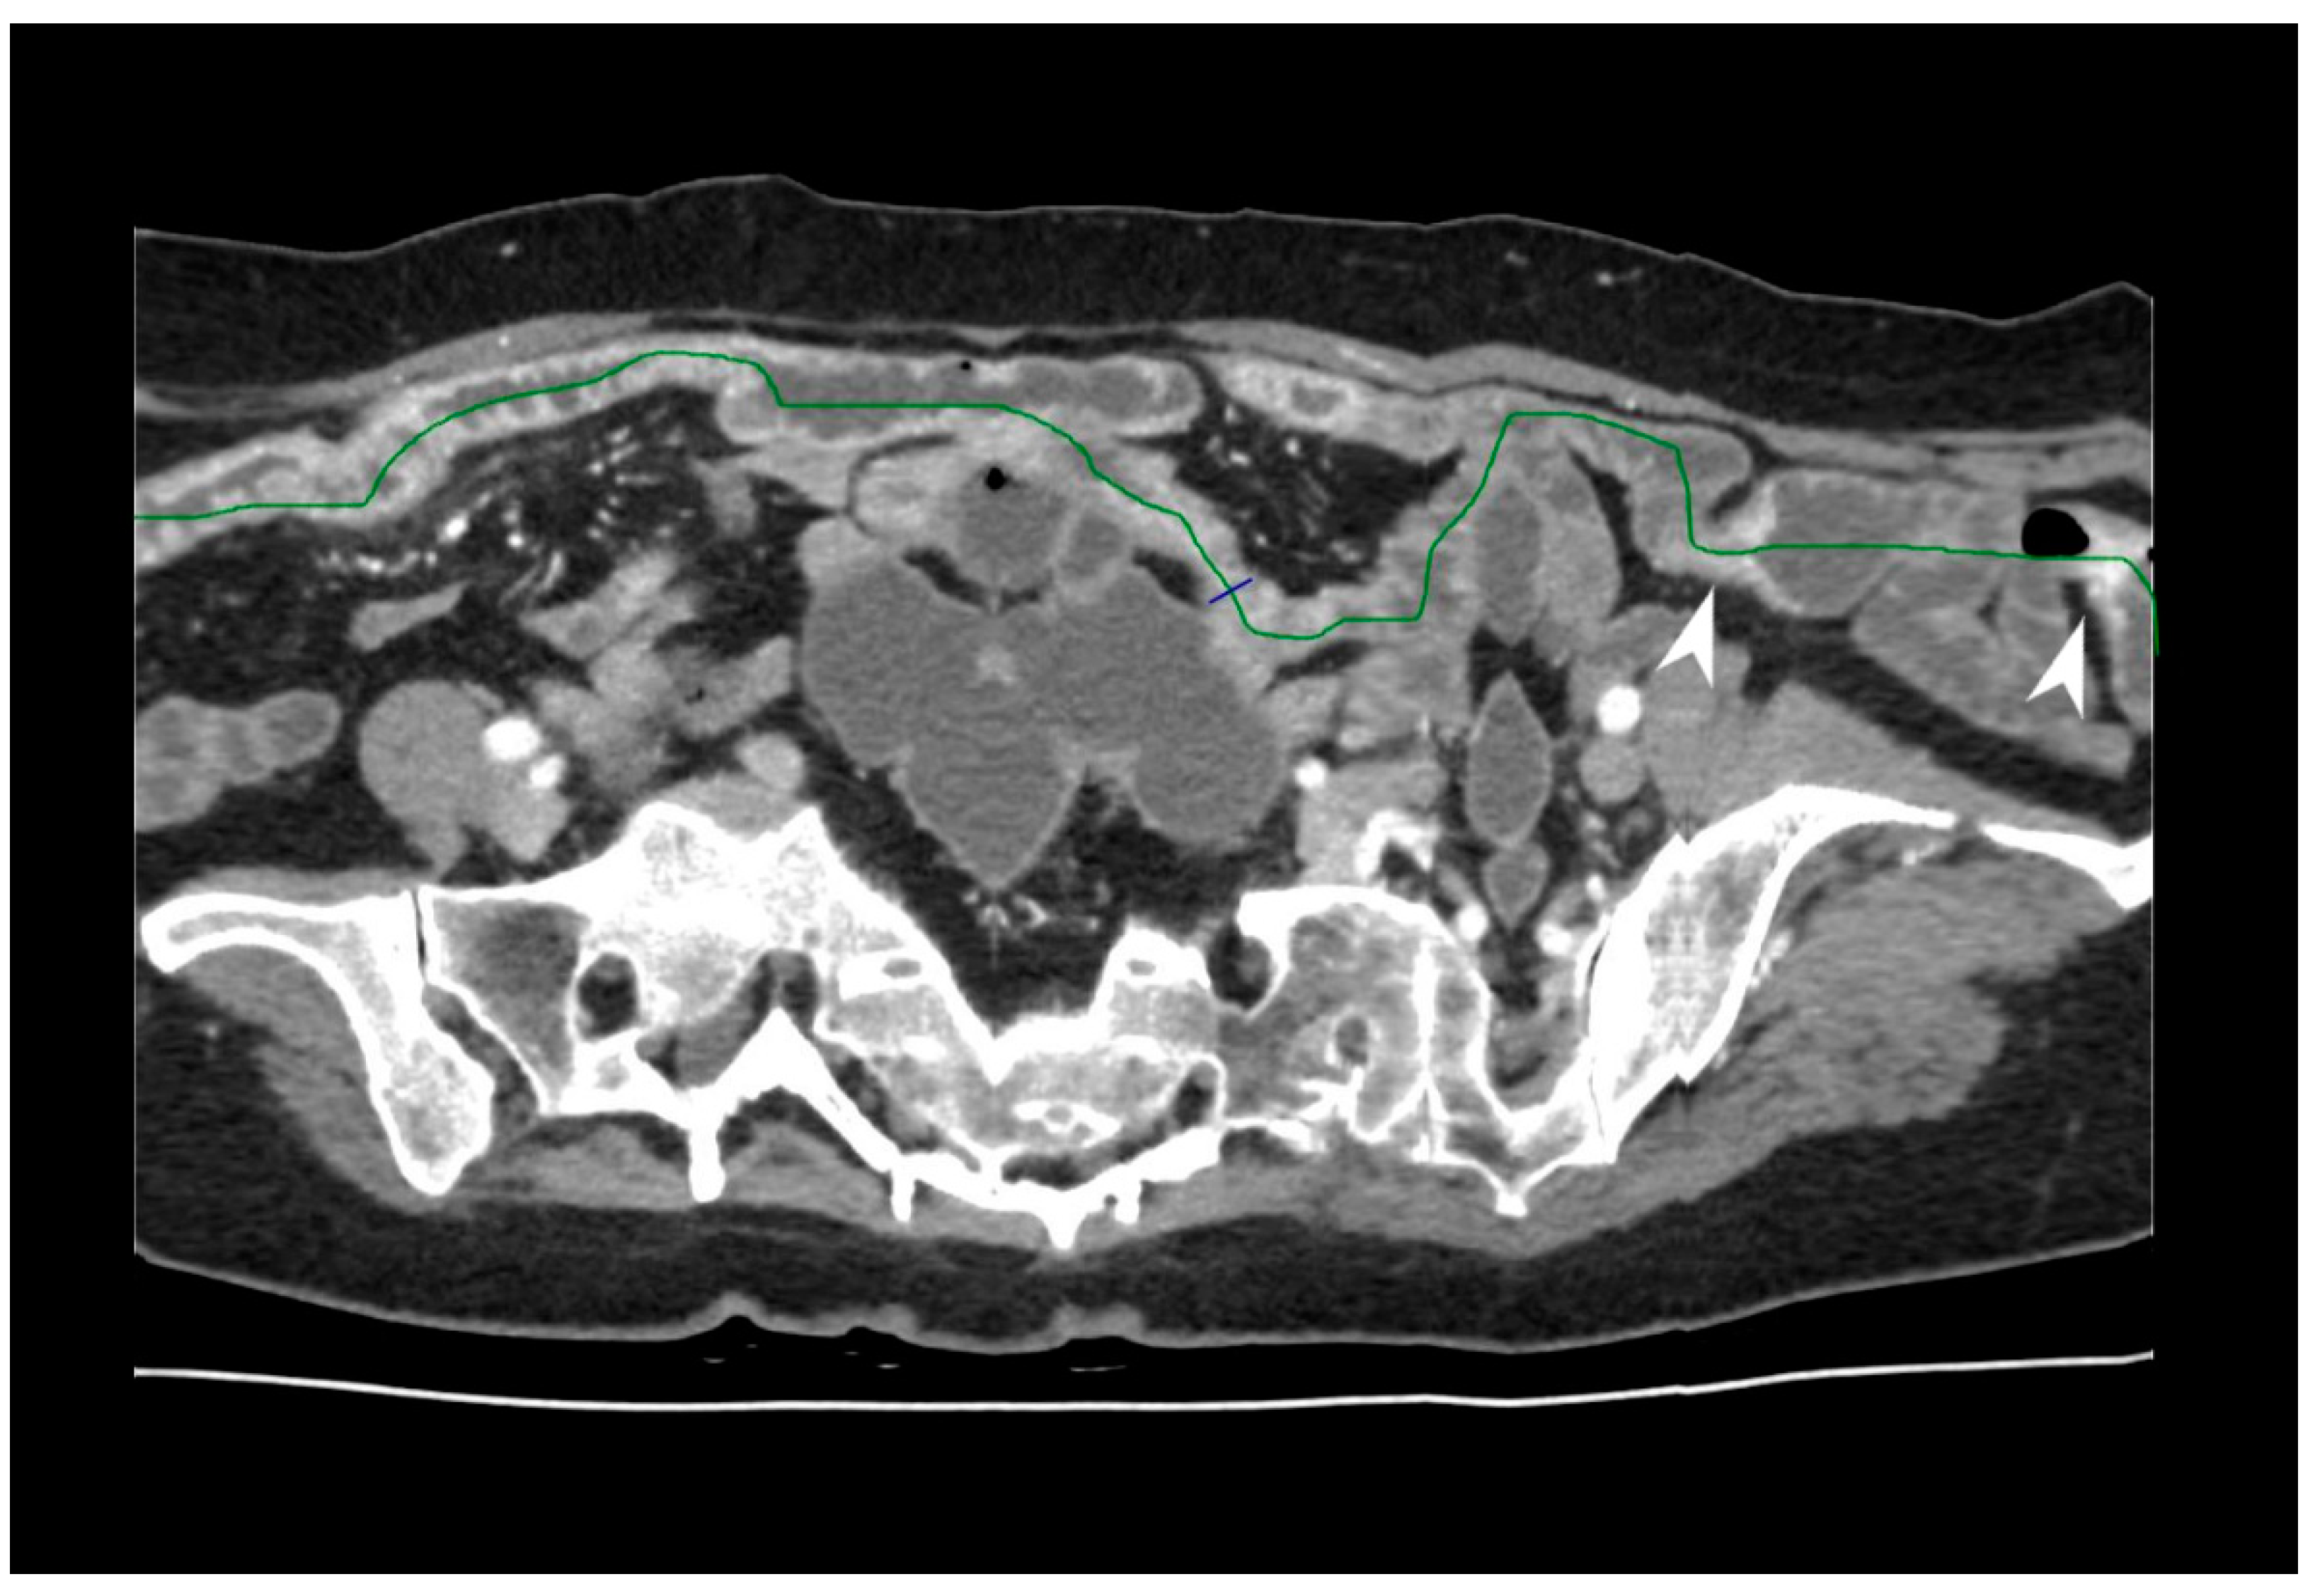

5.3. Fistulising/Perforating Subtype